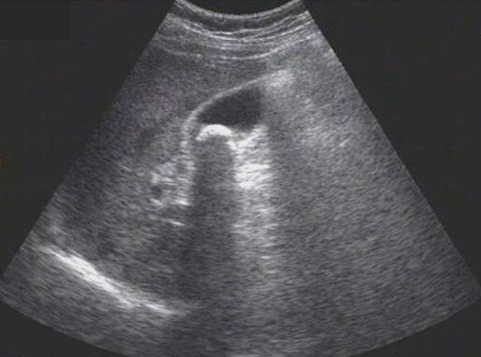

試題3:患者女性,50歲,間斷上腹隱痛半年,診斷為(2分)

A.肝癌

B.肝硬化

C.膽囊結(jié)石

D.腎結(jié)石

E.急性膽囊炎

【答案】C